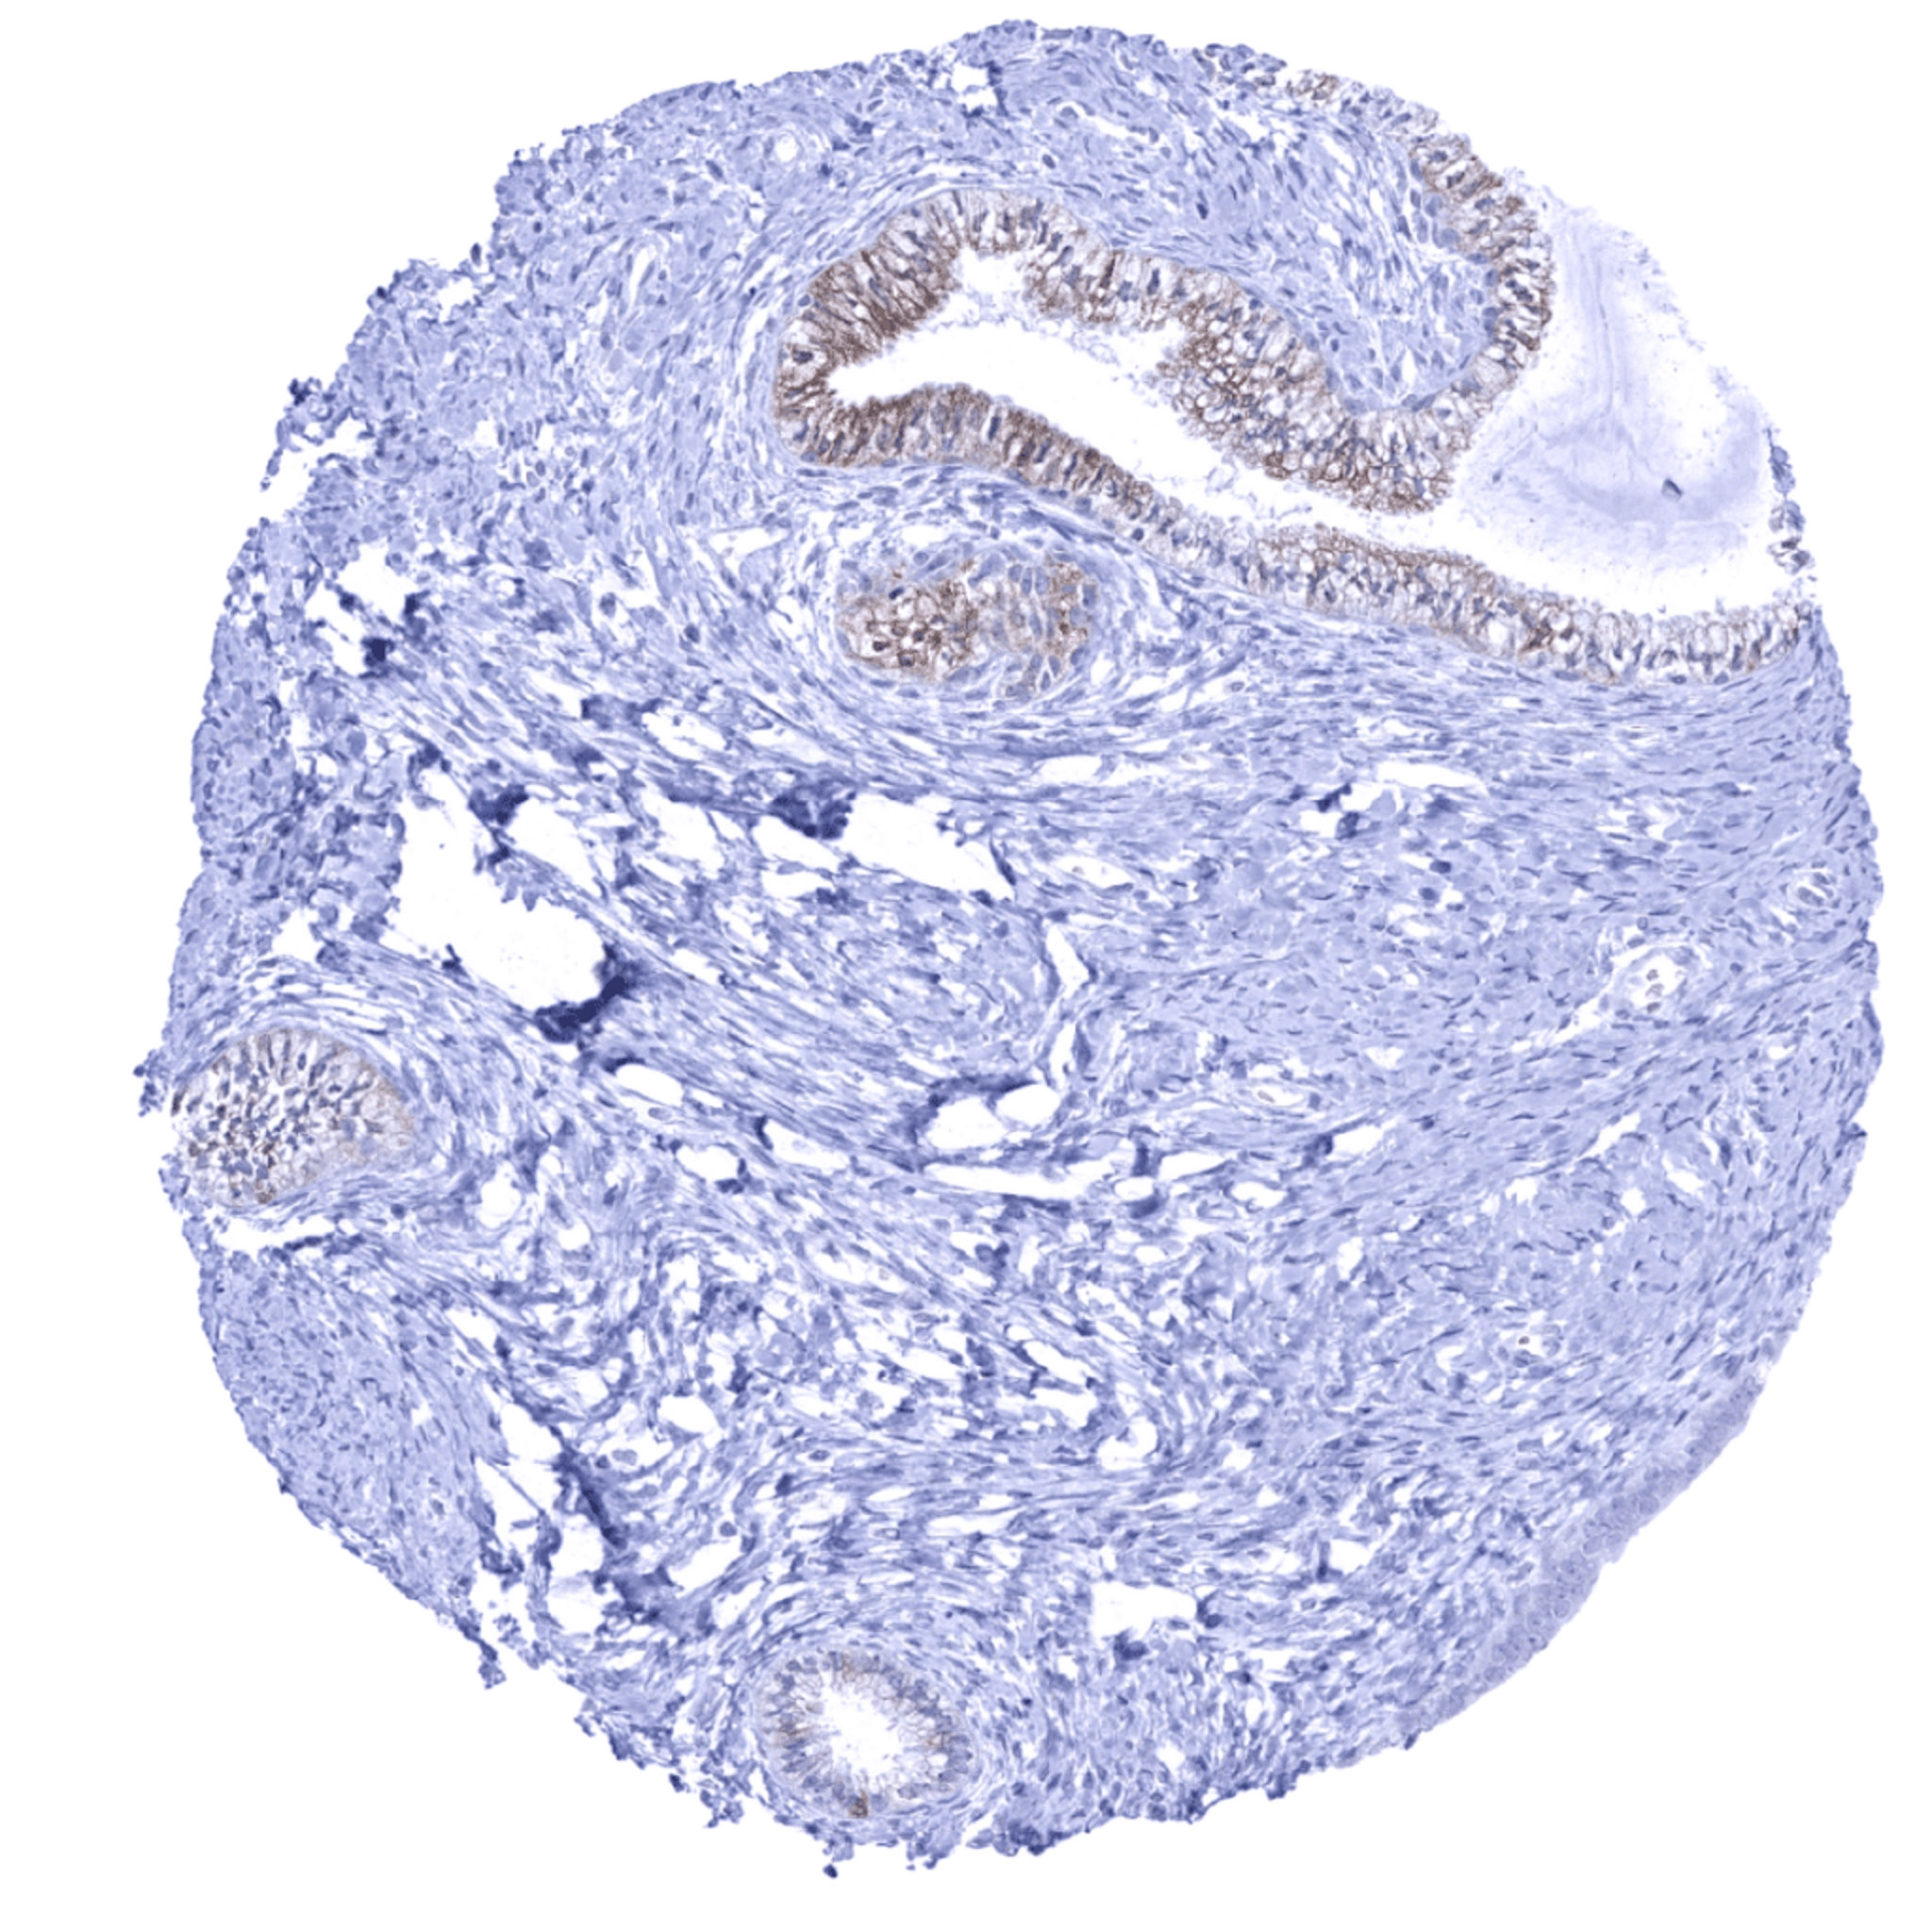

Uterus, endometrium – Strong UPK1B staining of some glands while others are completely negative

Uterus, myometrium